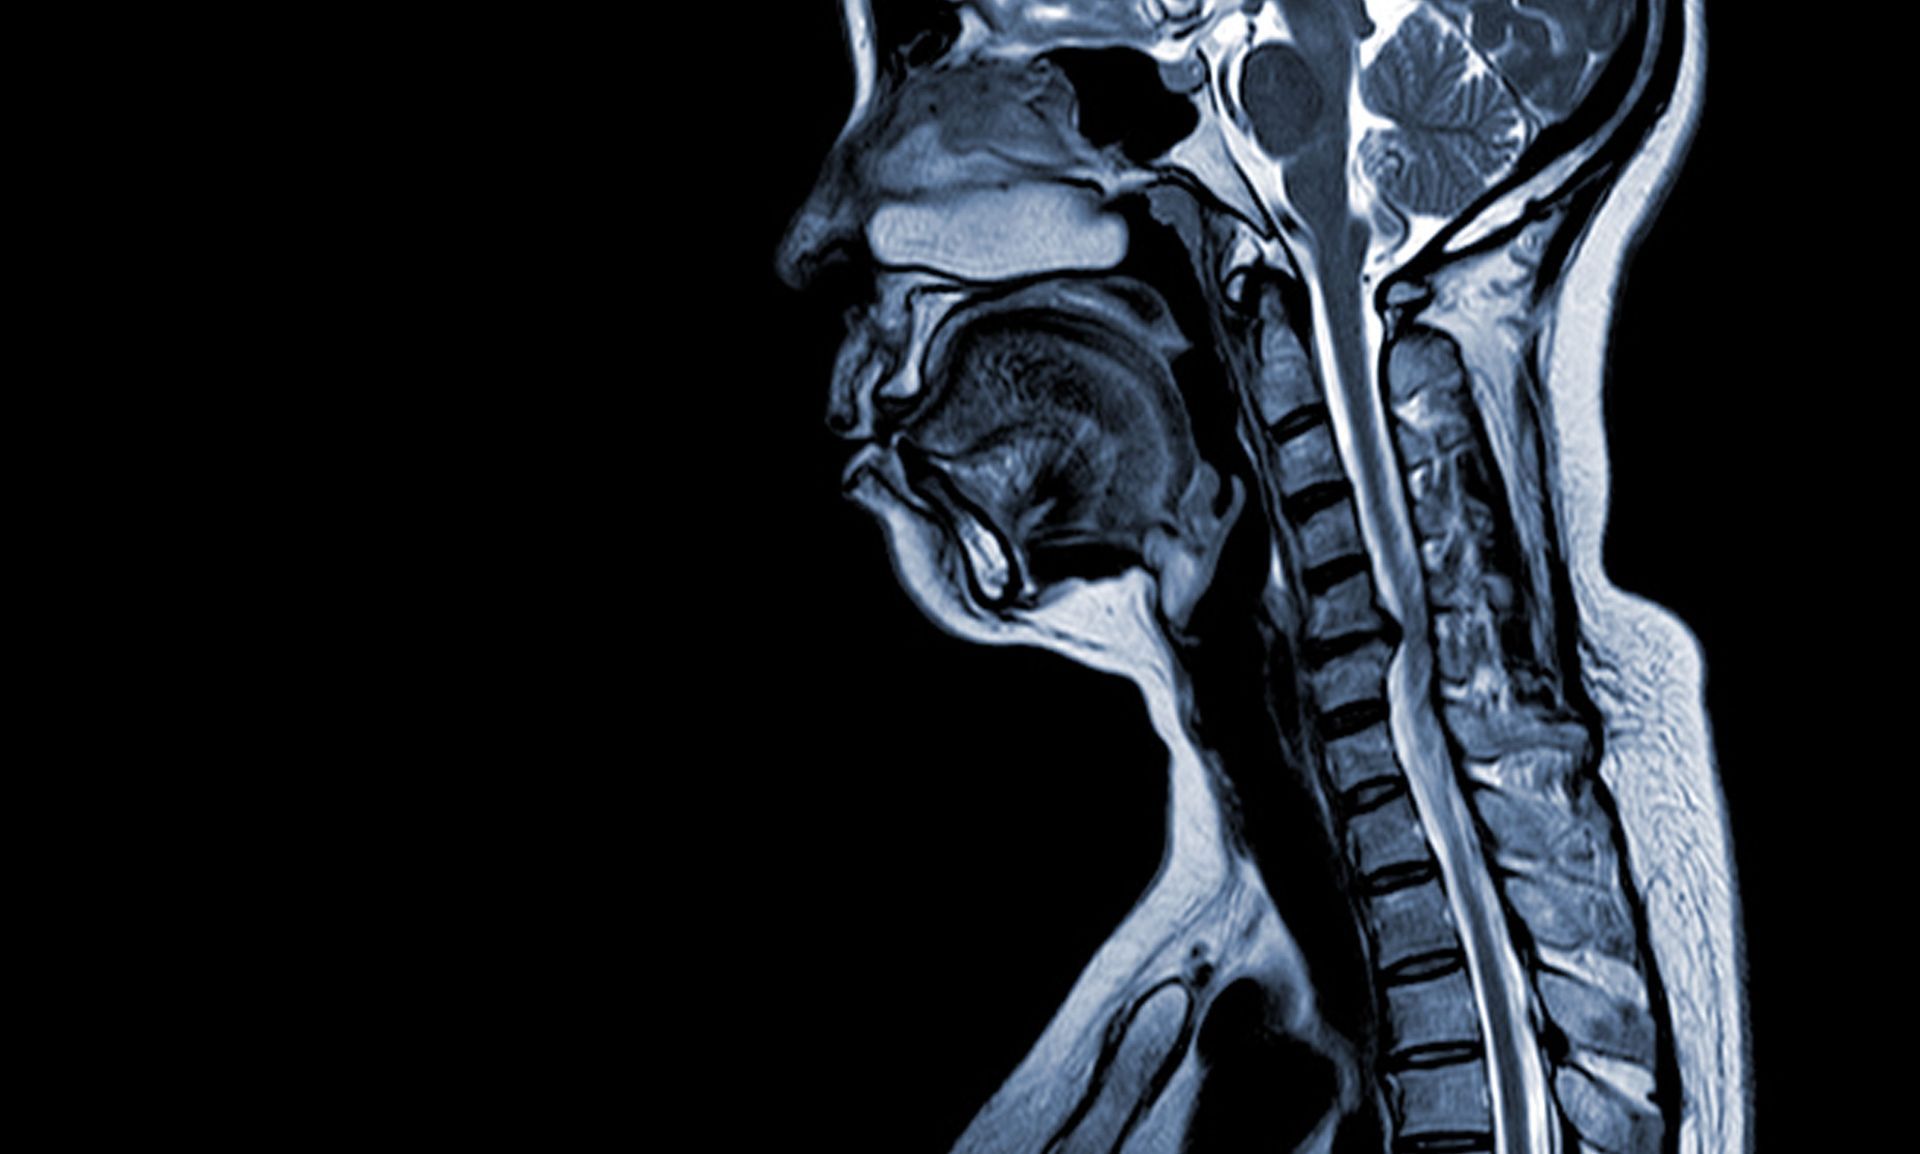

The diagnostic process often involves a CT or MRI scan, through which the location and severity of the herniated disc can be adequately assessed.